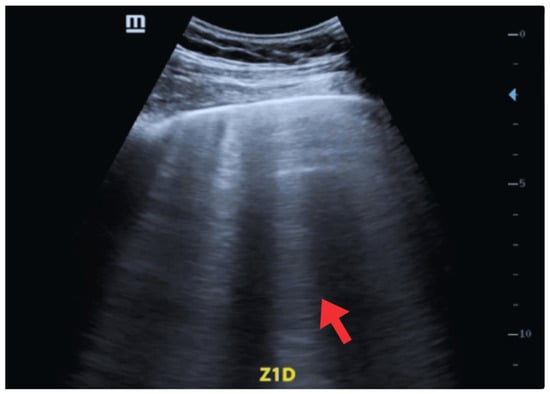

| 5 May | Acute episode of oppressive retrosternal chest pain (30 min, 8/10), with sudden moderate dyspnea, nausea, and profuse diaphoresis. He presented to the primary emergency department. Initial evaluation: BP 160/85 mmHg, SatO2 85%, signs of pulmonary and peripheral congestion. | -ECG: Biphasic T waves were present in the anteroseptal leads (V2–V4), consistent with a type A Wellens pattern. -Laboratory: elevated troponin I (0.16 ng/mL), (reference < 0.03 ng/mL). | POCUS: Ejection fraction of 40% (moderate systolic dysfunction), shortening fraction of 18%, EPSS of 10 mm, lateral wall hypokinesia, eccentric remodeling with ventricular dilatation, thickened interventricular septum, and a small non-circumferential pericardial effusion. At the lung level, diffuse B lines (50–60% of lung fields) were present, a pattern consistent with alveolar-interstitial syndrome of cardiogenic origin. | Initial treatment: oxygen, IV nitroglycerin, ASA 300 mg PO, clopidogrel 300 mg PO, rosuvastatin 40 mg PO, IV furosemide. |

| 6–7 May | Mild retrosternal chest pain, absence of dyspnea, and improved ventilatory mechanics. | ECG: Biphasic T waves were present in the anteroseptal leads (V2–V4), consistent with a type A Wellens pattern. | POCUS: Decreased pulmonary B lines in both lung fields (40–50%). | Referral to a more complex center. Enoxaparin 80 mg SC every 12 h is added. |